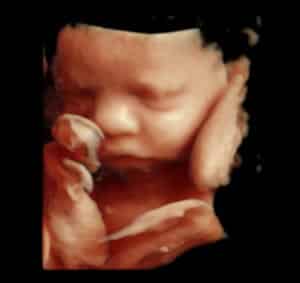

Explore our Photo Gallery and see the real results from Knit 4D Ultrasound. Every image you see  from 2D, 3D, 4D, to HD live ultrasounds  was captured by our highly trained team using our state-of-the-art ultrasound machine. We can begin creating amazing 3D/4D keepsake images as early as 8 weeks, giving you a beautiful first look at your baby.